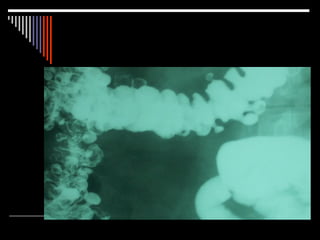

ECTASIA VASCULAR

 ANGIODISPLASIA COLONICA.

 REPRESENTAN UNA CAUSA FREC. DE H.D.B.

AGUDA, CRONICA, OCULTA.

 MAS FRECUENTES EN COLON DERECHO.

 DIAGNOSTICO: COLONOSCOPIA O ANGIOGRAFIA.

 ¾ COLON DERECHO.